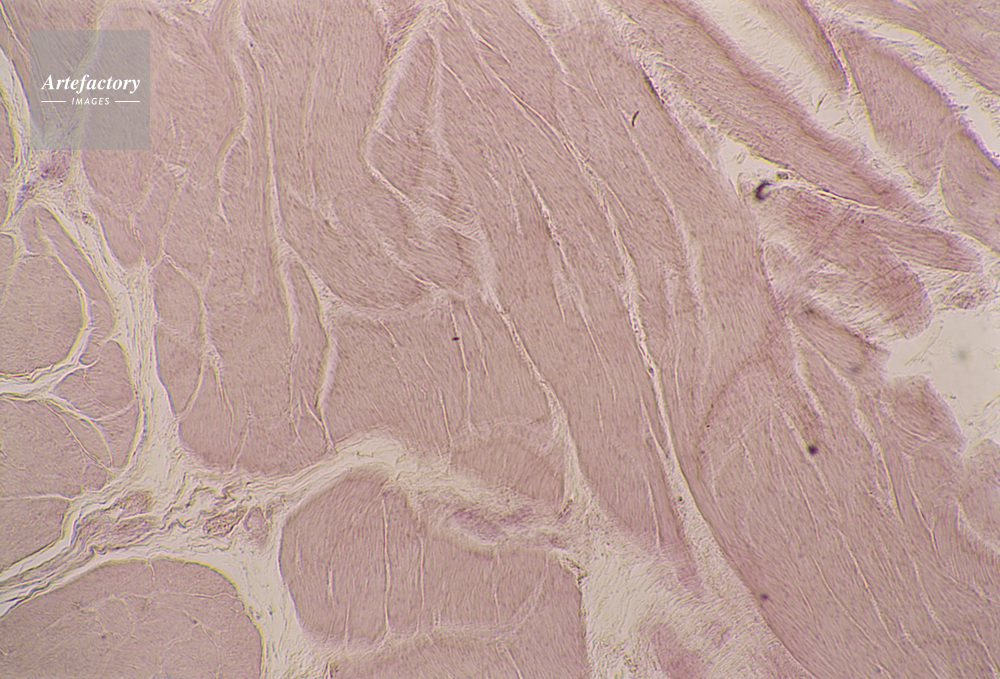

| キャプション | 平滑筋,40倍 | 制限事項 | ||